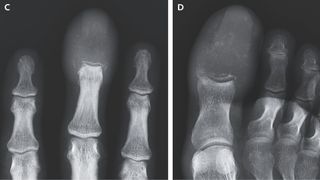

Weird swelling of man's fingers and toes revealed cancer had 'completely replaced' the bones with lesions

Marked swelling in a man's finger and big toe was a symptom of late-stage cancer.